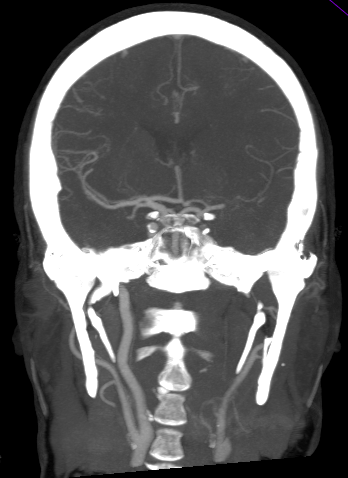

ANGIOGRAFÍA TC.

Sirve para:

- Definir el lugar de oclusión.

- Descartar disección arterial.

- Grado de colateralidad.

- Grado de arterioesclerosis.

Con la información aportada podremos pronosticar mejor la localización y extensión del infarto. Además, proporciona un mapa vascular para el tratamiento endovascular.

- Adquisición desde cayado de aorta hasta vértex (importante para observa variantes del cayado y morfología de los vasos cervicales)

b) Estudio:

- MIP de 25mm en Polígono, con reconstrucciones en planos básicos.

- Reformateo curvo para vasos cervicales (segmento cervical de las carótidas, arterias vertebrales)

c) Objetivo:

Es importante leer el estudio orientados por la clínica y los hallazgos de la TC sin contraste. Aún así, es conveniente seguir una sistemática para estudiar todos los vasos importantes y no pasar por alto la patología.

La angioTC nos sirve para:

- Estudiar morfología del cayado y variantes + descartar estenosis en bifurcaciones carotídea. Datos muy importantes de cara para el intervencionismo.

- Detectar disección arterial (produce ictus por suelta de embolos o por oculisón hemodinámica)

- Valoración de Polígono de Willis: patología (estenosis, aneurismas, malformaciones) y sus variantes de la normalidad (informar de la existencia de comunicantes, dominancia, ACoP de origen fetal, etc…)